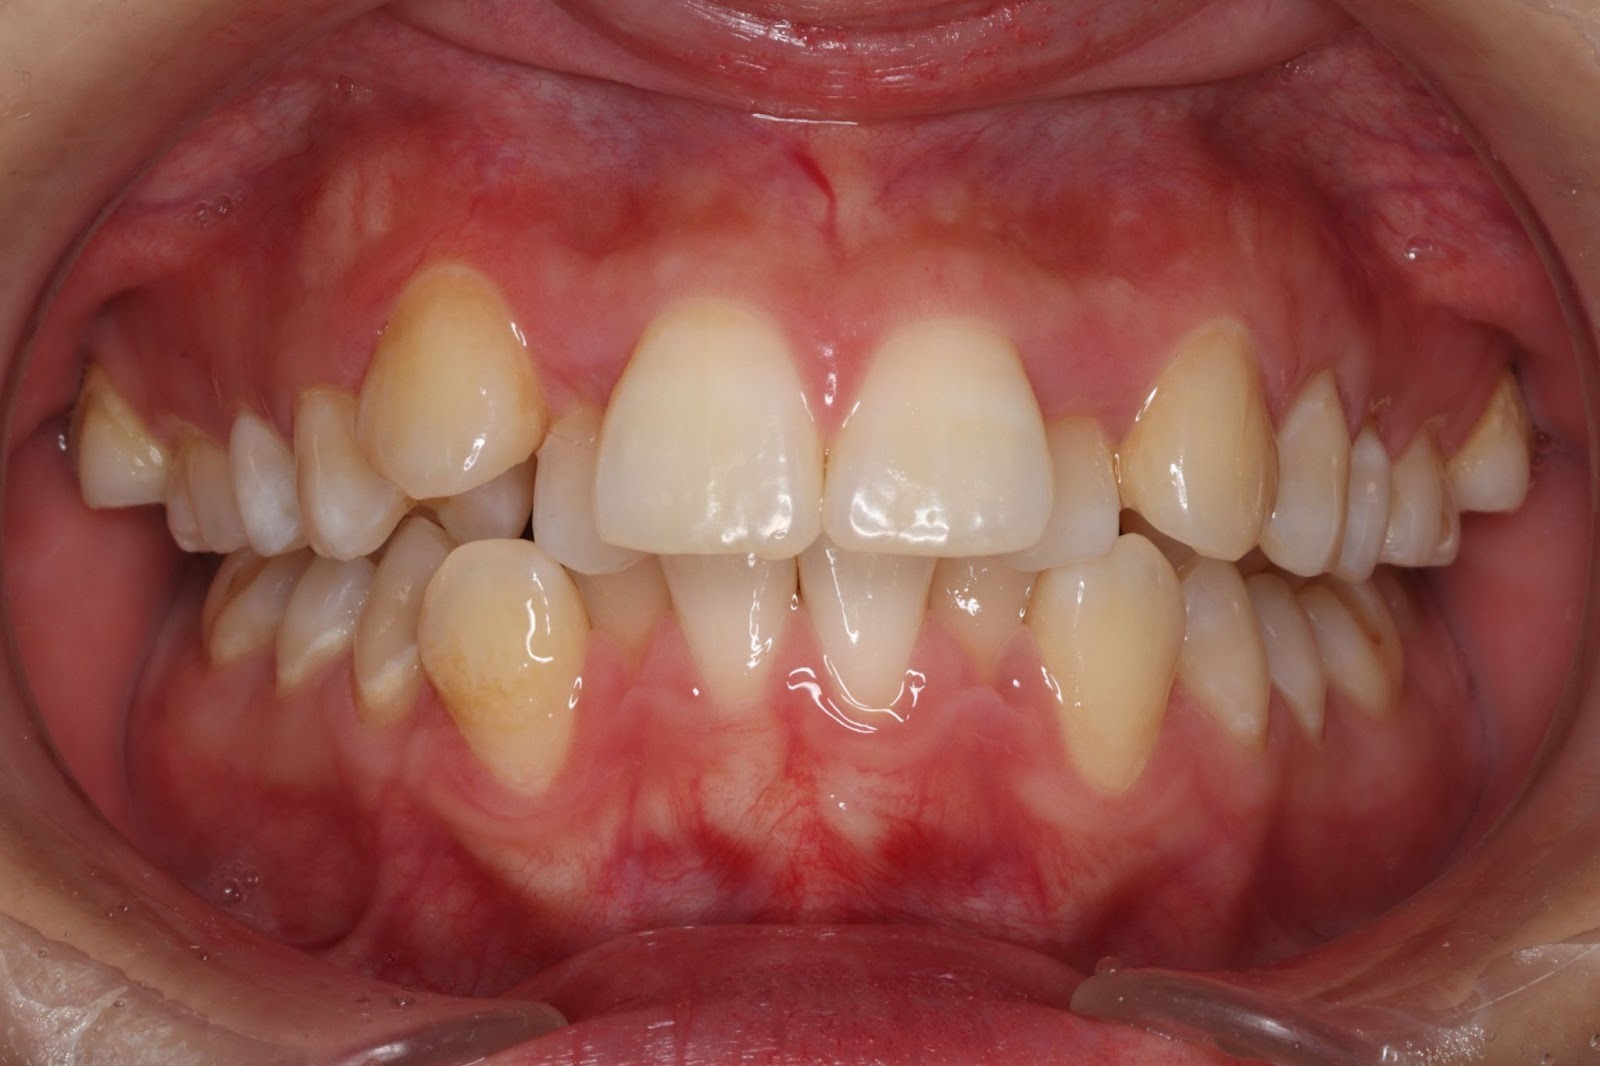

重度の叢生の方

マウスピース矯正は、歯を“少しずつ”動かす仕組みなので、歯並びのズレが軽度〜中程度である場合に最も適しています。例えば、歯が大きく重なっている「重度の叢生(そうせい)」「八重歯」「大きな出っ歯や受け口」「深い噛み合わせ(過蓋咬合・開咬・クロスバイトなど)」「左右の非対称」など、複雑で高度な歯列不正がある場合、マウスピースのみでは対応できないことがあります。

また、歯を大きく動かしたり回転させたり、根元から動かすような移動が必要な場合も、力の制限があるマウスピースでは、治療効果が弱かったり、期間が長くなったりする恐れがあります。

このような「大きな歯の移動が必要」「骨格的な歯列不正」の人は、無理にマウスピース矯正を選ぶと期待した効果を得づらいため、ワイヤー矯正や外科矯正などをおすすめされることがあります。